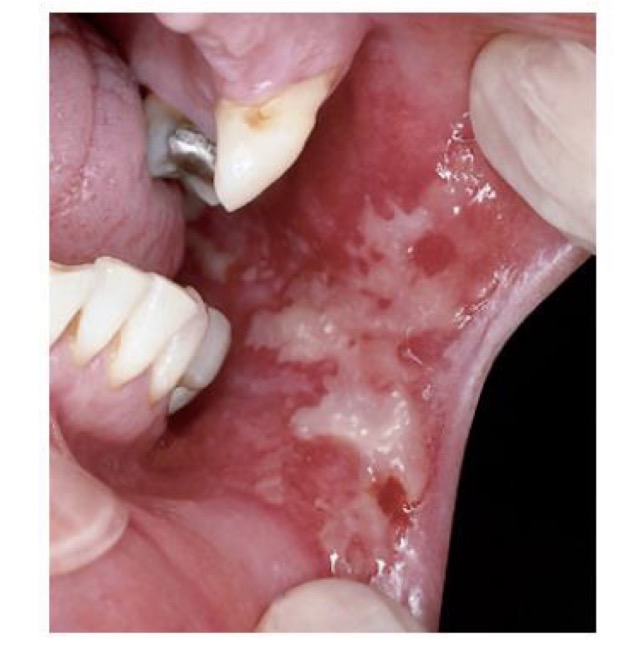

BN SAU XẠ TRỊ

NIÊM MẠC SƯNG NỀ, ĐỎ, LOÉT VÀ ĐAU

CHẨN ĐOÁN?

VIÊM NIÊM MẠC MIỆNG DO TIA XẠ (ở niêm mạc má )